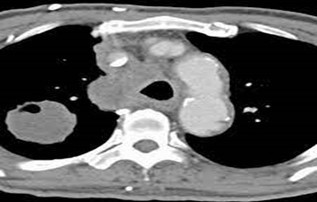

- CECT thorax showed right upper lobe lung mass and bulky mediastinal nodes (Figure 2).

Figure 2- Right upper lobe lung mass with bulky mediastinal nodes